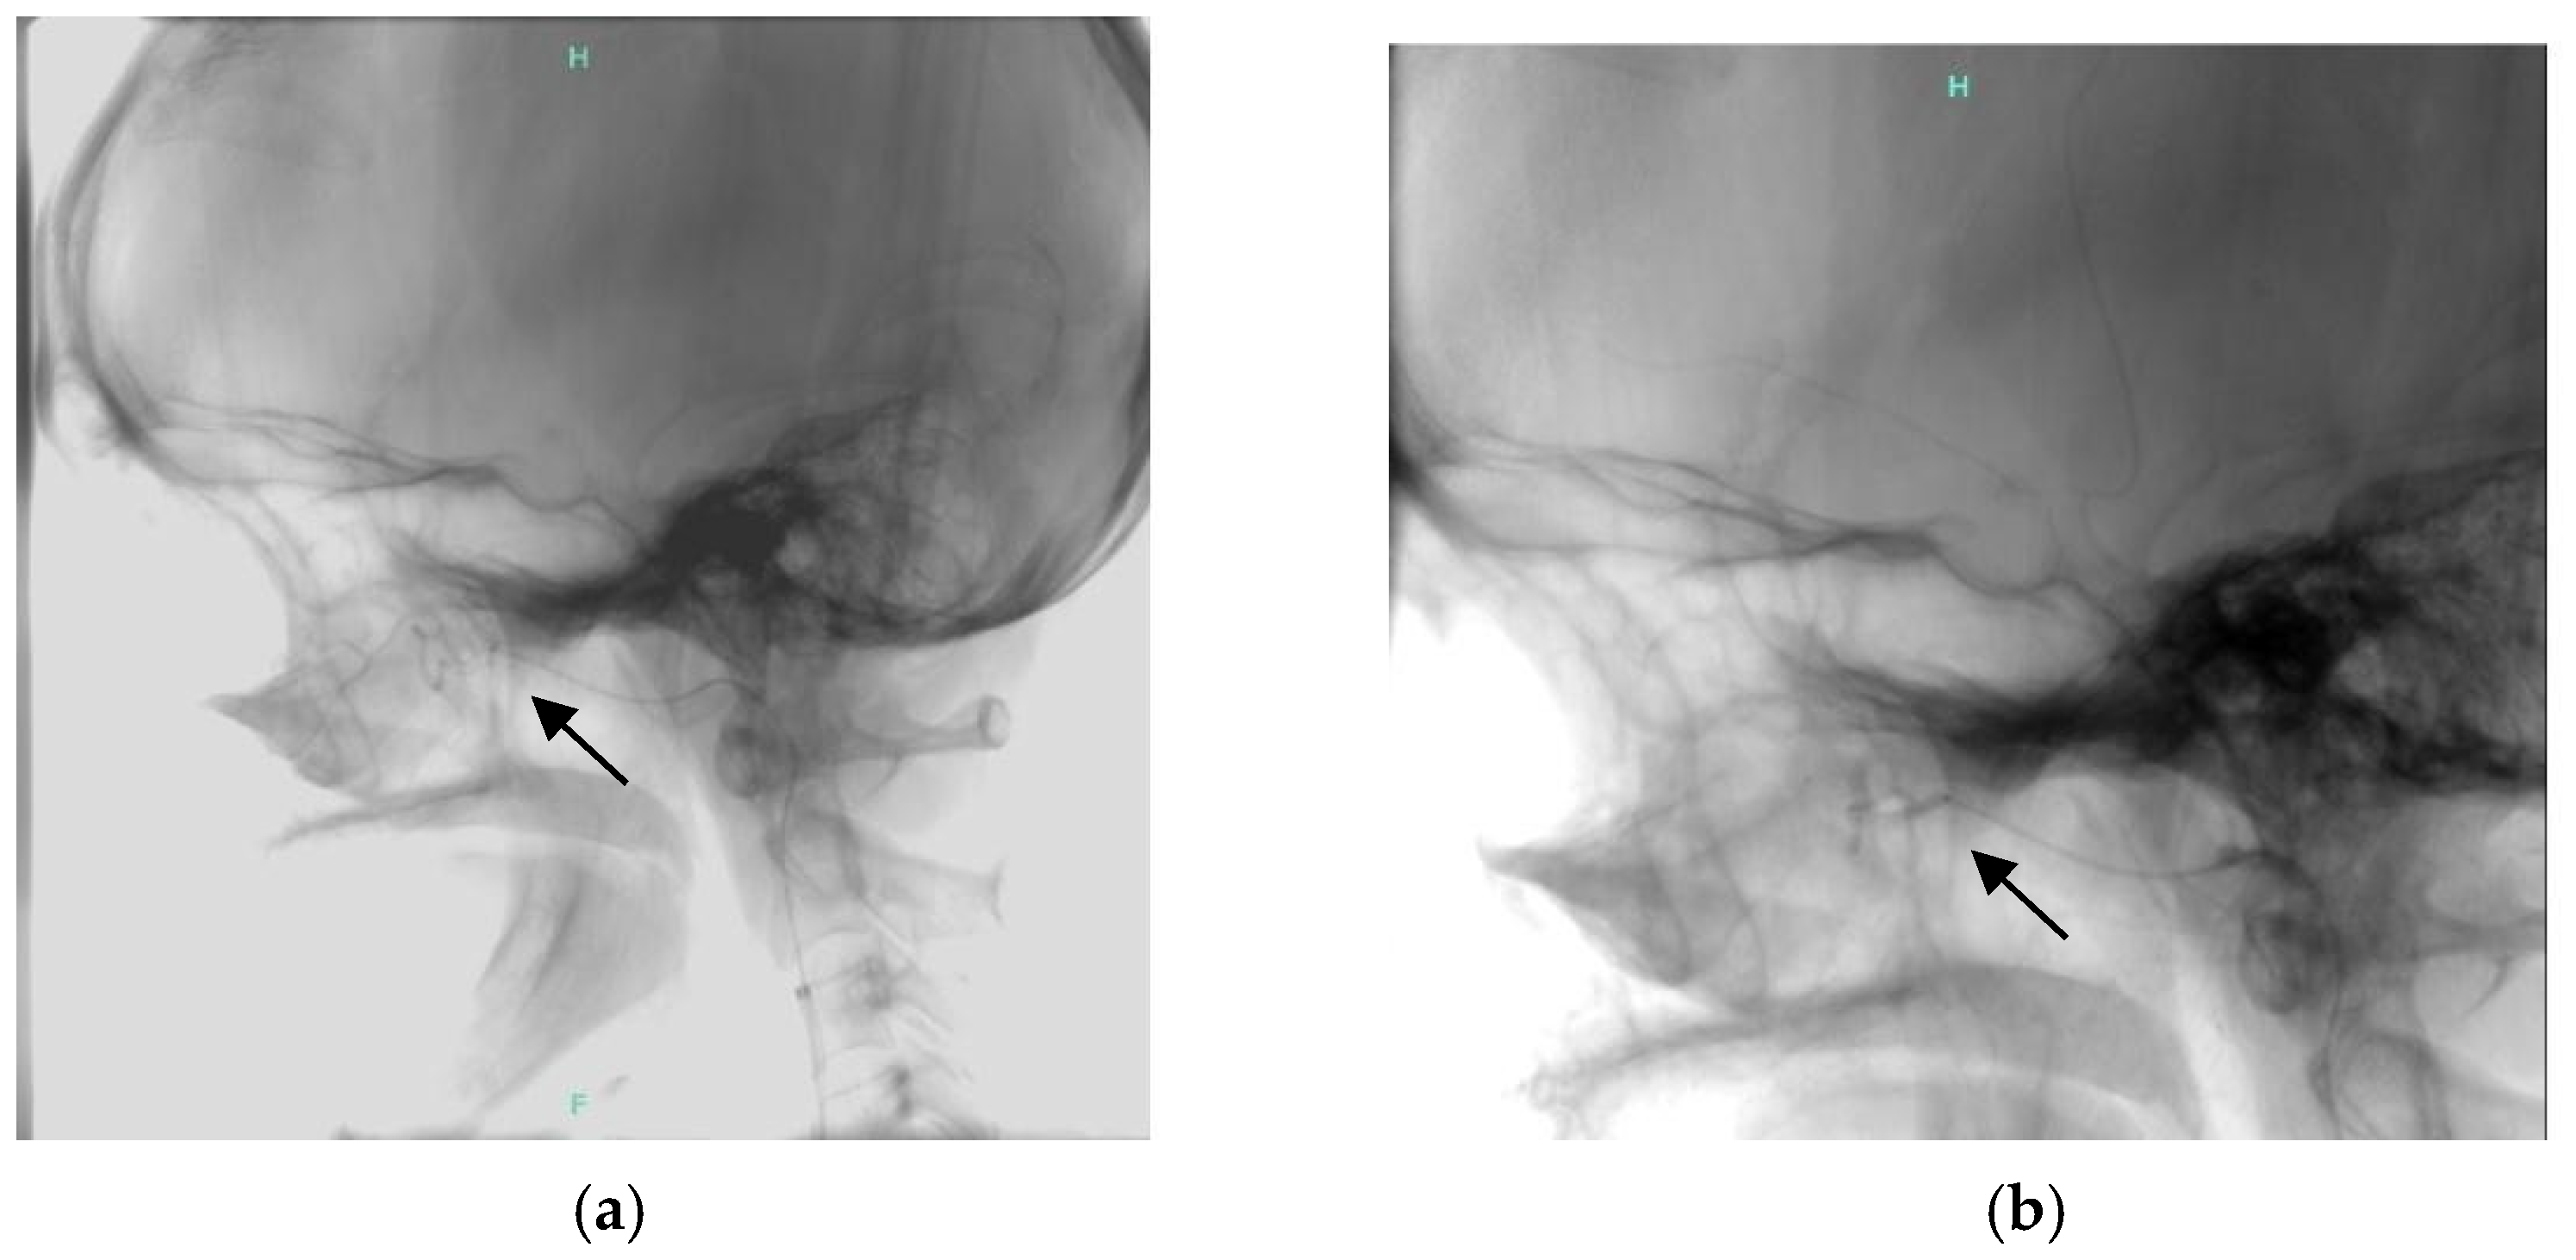

3.3. Case Report